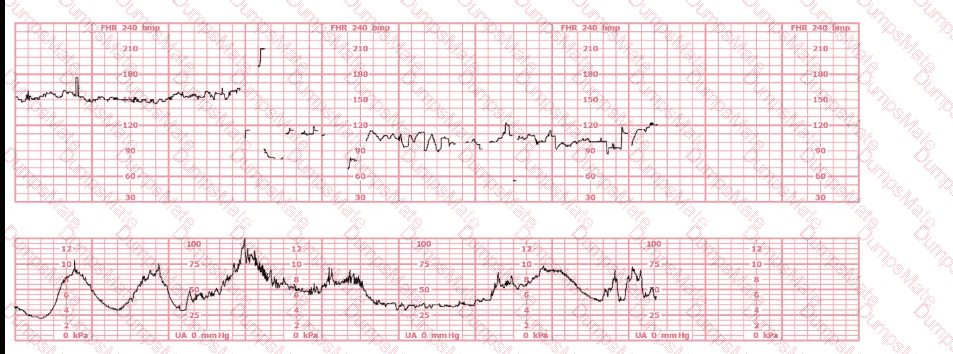

Questions 9

A woman at 41-weeks gestation is being induced. She is 2 cm dilated and is on oxytocin at 8 milliunits/minute. Based on the fetal heart rate tracing shown, the best initial response is to:

EFM Question 9

Options:

A.

Continue to observe

B.

Decrease the oxytocin

C.

Place a fetal spiral electrode

Buy Now